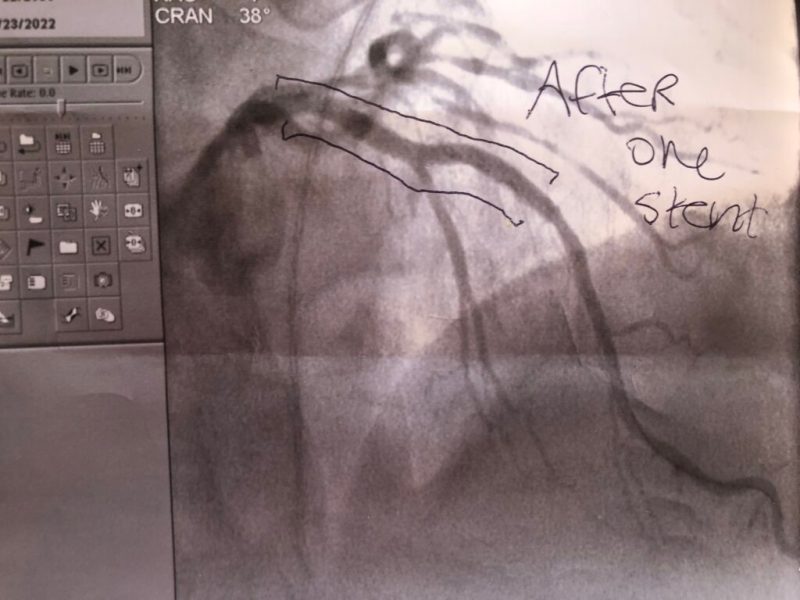

How do I know this was deadly serious? They gave my wife the before and after images. The arrow on the before points to the peak of the blockage. Note the massive difference in blood flow in the after.